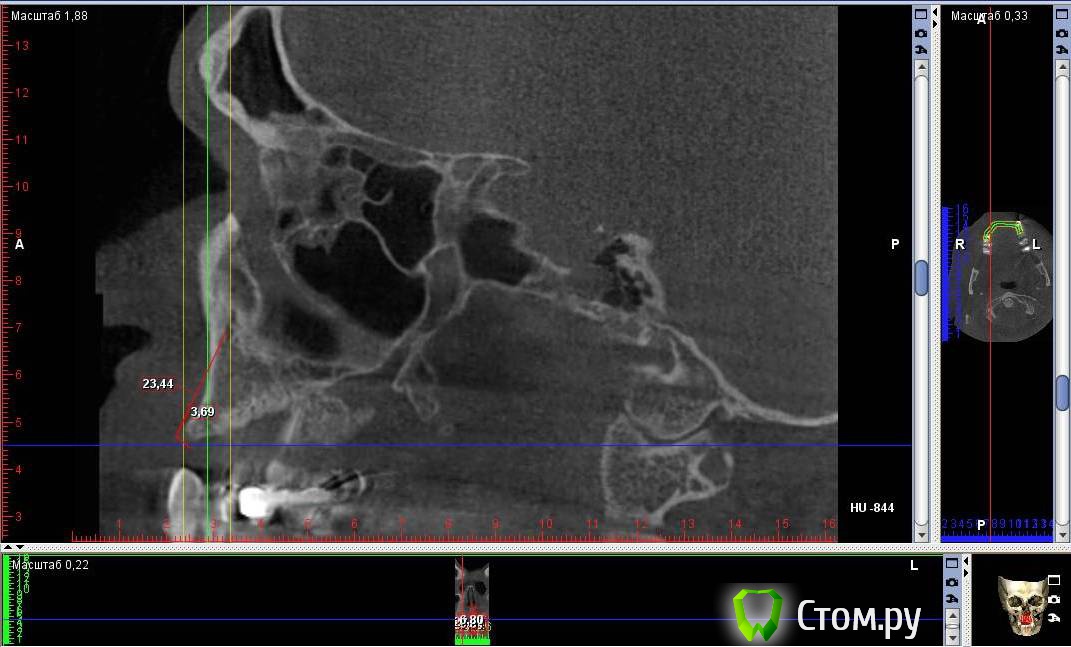

Togha Опубликовано 5 мая, 2014 Поделиться Опубликовано 5 мая, 2014 (изменено) Коллеги, обратился пациент, первый этап работы - устранение адентии между 14 и 23 зубами. По вертикали есть куда разбежаться (до анатомических образований от 17 и более мм), но вот гребень совсем узкий (от 2 до 5 мм), а также широкий резцовый канал (примерно 6.5 мм в диаметре). Между 14 и 23 расстояние 38 мм. Пациент решительно настроен на имплантацию. Хотел бы узнать, какую методику аугментации посоветуете, и как спозиционировать имплантаты? Склонялся к расщеплению гребня, нкр, имплантаты 3.75 мм на 10 мм, сделать мостик предлагает ортопед, на область 13, 11, 21, 22. Но как с расщеплением в зоне резцового канала и куда ставить имплантат 21 (как видно, есть значительное смещение канала от 11 в сторону 21), прямо в канал? Ссылка на DICOM файл http://yadi.sk/d/2vcbkBjaPBRgMСсылка на образ диска с просмотрщиком http://yadi.sk/d/csIsw0mYPBS2x На второй картинке примерно обозначен граница резцового отверстия вертикальными линиями Изменено 5 мая, 2014 пользователем Togha Ссылка на комментарий